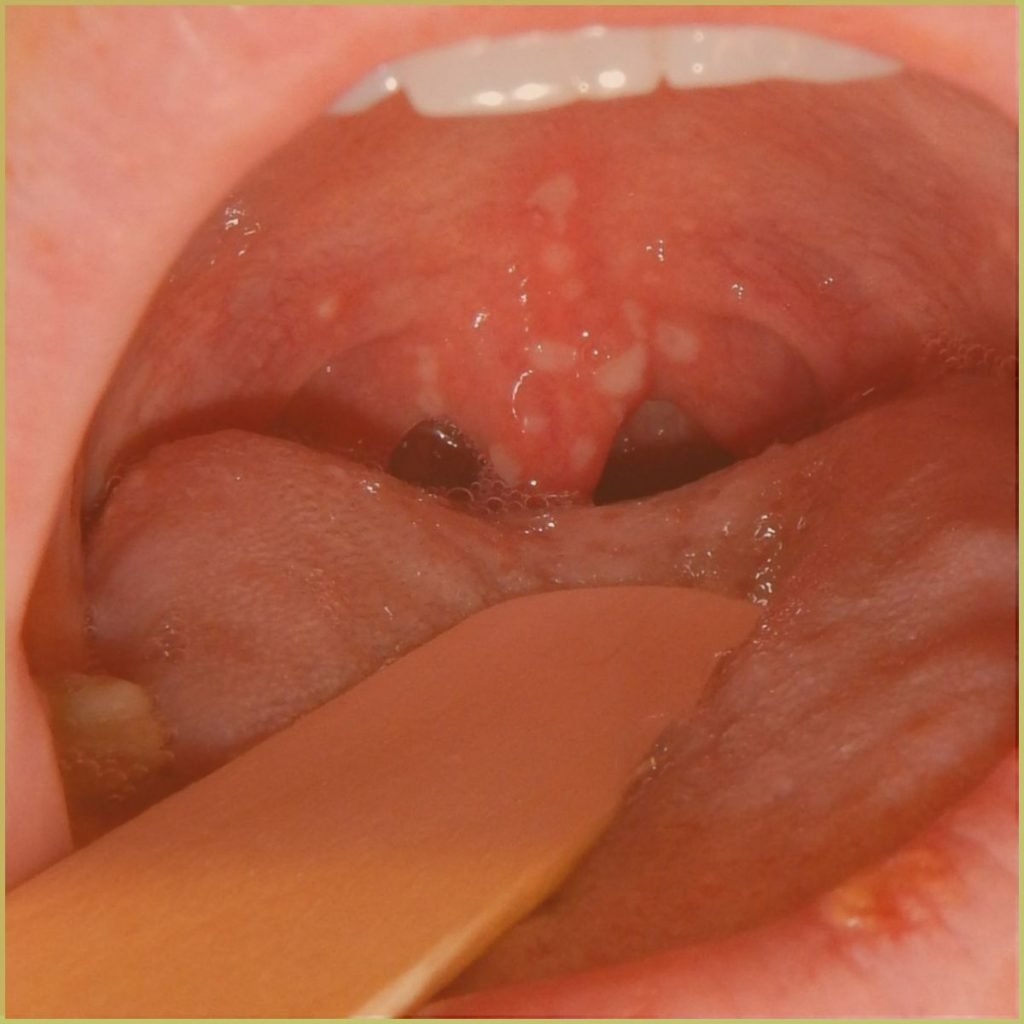

HERPANGINA

Herpangina is a highly contagious disease usually caused by a coxsackie (A and B) virus infection. Though primarily a pediatric disease it may present in newborns, adolescents, and young adult patients. The common clinical presentation includes

- Incubation period of 5 to 9 days, resolves within 2 weeks.

- Acute onset of symptoms that involves the posterior oral cavity.

- Macular erythematous areas precede short-lived vesicular eruption, followed by ulceration.

- Pharyngitis, dysphagia, fever, malaise, headache, and lymphadenitis.

Diagnosis is usually based on the lesion history and clinical presentation only. Your differential diagnosis should include:

- Hand-foot-and-mouth disease.

- Varicella (chicken pox).

- Acute herpetic gingivostomatitis.

The disease is self-limiting and treatment is usually palliative only.